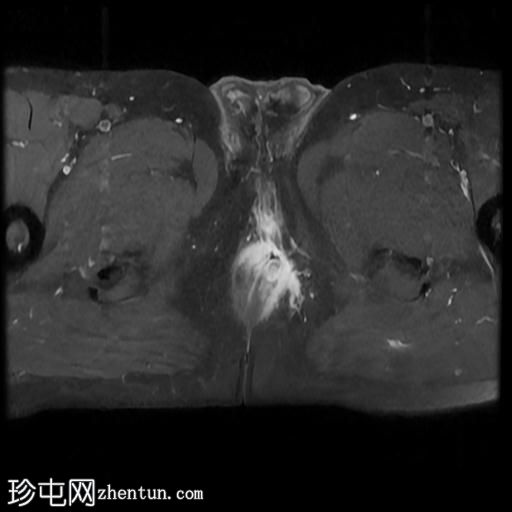

MRI

轴向位T2

脂肪饱和度

一条68毫米厚的强化通道始于左侧肛周区域,向上穿过肛门内外括约肌,在2点钟方向开口于肛管。

无脓肿形成。

MRI成像特征与所述左侧经括约肌肛周瘘相符。